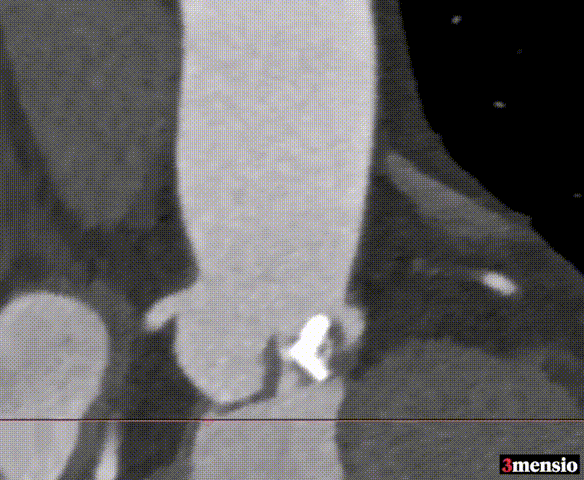

冠脉测量

冠脉开口高度可,切线角度测量,

左窦瓣叶长于LCA开口到瓣叶根部距离

连续时相观察左窦瓣叶动度灵活,

收缩期瓣叶接近左冠开口高度;

3D打印模型22mm球囊扩张测试,左窦冗余空间小